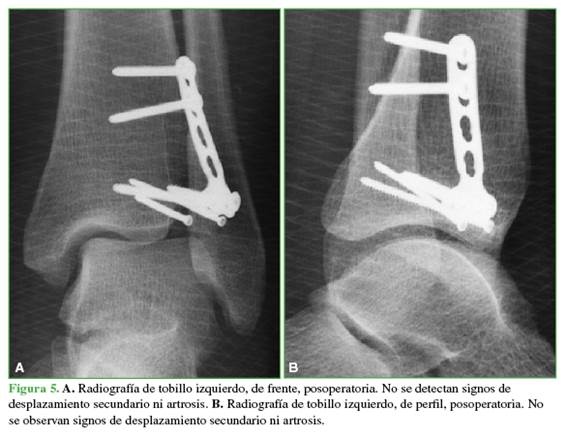

Se realizaron controles radiográficos seriados a los 15 días, al mes, a los tres meses y al año de la cirugía (Figura 5).

Un año después de la cirugía, el rango de movilidad era comparable con el contralateral y el puntaje de la AOFAS (American Orthopaedic Foot and Ankle Society) era de 90/100, debido al dolor esporádico con las actividades deportivas.